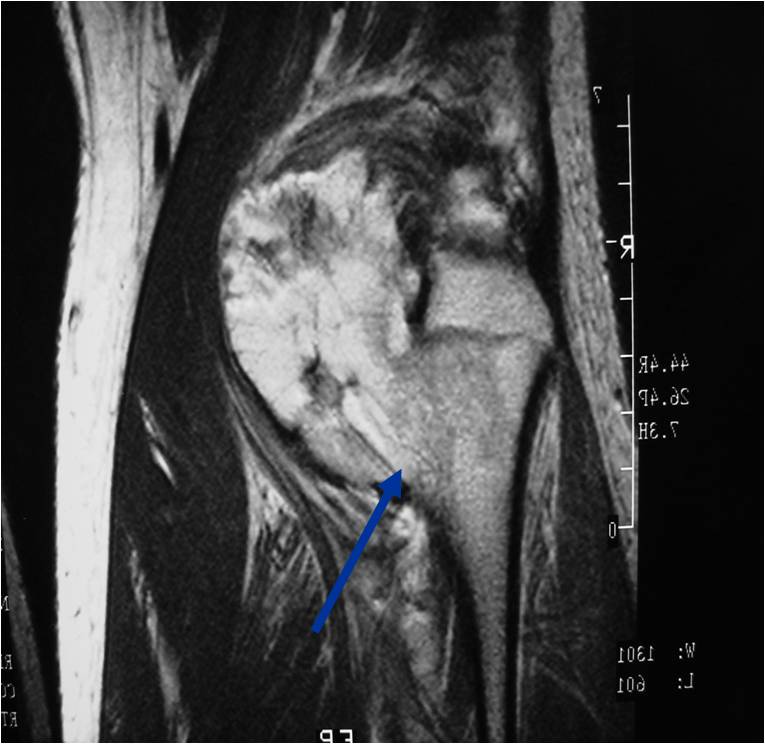

Osteochondroma Vs. Secondary Chondrosarcoma

The cartilaginous cap deserves the most attention when differentiating a benign osteochondroma from a secondary chondrosarcoma that arose from a pre-existing osteochondroma

In adults, the cartilaginous cap regresses and becomes thin due to enchondral ossificastion of the majority of the cap.

Malignant transformation is suggested by:

- Cartilaginous cap thickness greater than 2cm

- Cortical destruction

- Backgrowth of the cartilaginous cap into the stalk or medullary canal

- Lysis of calcifications in cap

- Best test for evaluating thickness of cap and surrounding bursa

MRI: Secondary Chondrosarcoma of Proximal Femur: Thick Cartilage Cap (>2cm)